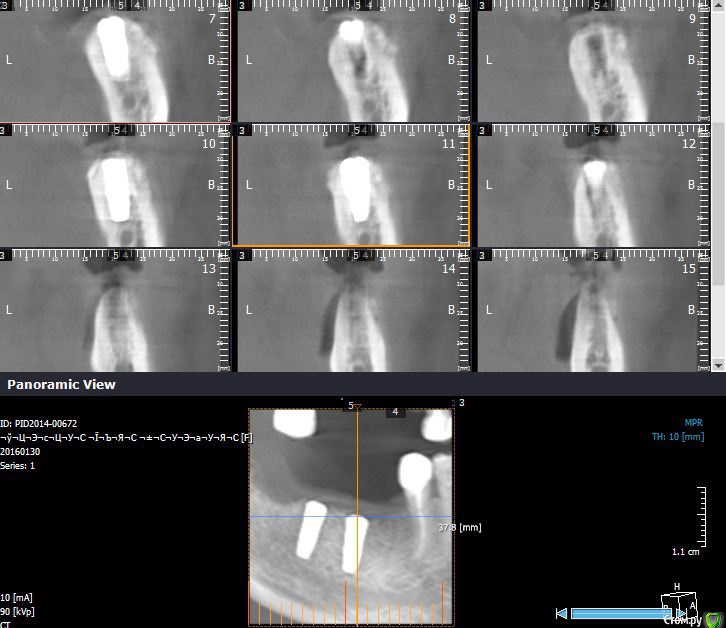

Endorphin Опубликовано 1 февраля, 2016 Автор Поделиться Опубликовано 1 февраля, 2016 Если возможно, то выкладывайте, пожалуйста КТ с измерениями в миллиметрах. А то совсем не понятно что там и как выросло. До аугментации. При такой форме не решился расщеплять. От вершины гребня до нерва не многим более 11 мм в среднем на протяжении дефекта. Ширина там, где хотелось бы видеть платформу 2-3мм. 5 месяцев после аугментации. Видно что частично графт скорее всего уйдет, так и вышло. Ширина 6.5мм, высота 12-13. немного не там где хотелось, но имплантация возможна. Контрольная кт после установки имплантатов. Dentium sl 3.8x10 3 Ссылка на комментарий